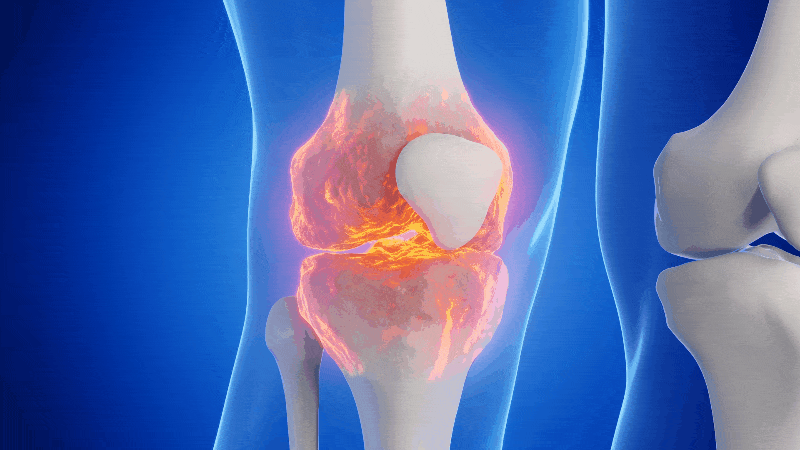

Cartilage doesn’t have nerves, so it can’t actually feel pain. That ache, stiffness, and swelling you’re feeling is coming from the tissues around it: the bones, muscles, joint capsule, bursae, ligaments, tendons and all the pressure that is caused by the swelling and inflammation in the area.

I = Inflammation

Chronic inflammation is like a low-grade fire inside your joints. It breaks down tissue and amplifies pain signals. And just like a fire, if you don’t put it out, it keeps spreading and destroying everything nearby.